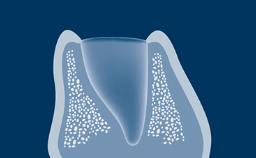

The esthetic aspects of implant prostheses have gained increasing attention and importance in recent years. There are a number of factors that determine if implant prostheses are considered esthetically successful by both the patient and the clinician.

With the aim of achieving optimal esthetics, this Learning Module will outline and discuss the determining factors related to esthetic planning for fixed dental prostheses or FDPs.

- describe peri-implant soft tissue factors that guide planning of esthetic implant-supported FDPs